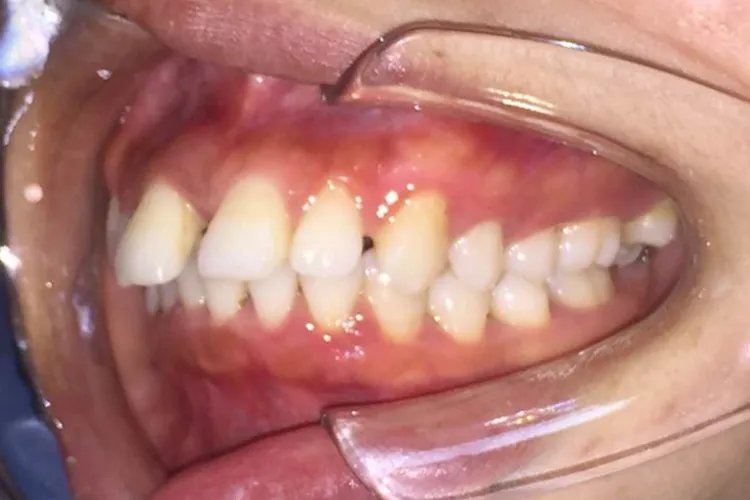

如果门牙较大,首先要尽早拔除智齿,否则可能会出现磨牙的情况,导致间歇过大。此外也可以采取金属牙托正畸的方式来治疗;不要为了图便宜方便,去不正规的机构镶牙,这样会出现不良修复体。平时也要养成良好的习惯,定时清洁牙齿,以及保证口腔卫生,也要掌握正确的刷牙方法。爱美人士都会因为门牙大所困扰,因为门牙大不但会让牙齿看起来牙列不齐,也影响整个人的个人形象,所以有些人会想要通过正畸的方式,来解决门牙大的情况,但有些不正规的诊所或者门诊,会让情况更加严重,那如果门牙大怎么办?该注意什么呢?一、门牙大怎么办1.尽早拔智齿部分门牙大的情况,可能是因为智齿倾斜,让前面的牙齿出现磨牙的情况,从而导致的间隙较大,所以尽早拔除可以有利于保护磨牙。2.正畸治疗如果门牙较大,可以用金属正畸托于患牙上,这样利用矫正的方式来关闭缝隙,也能恢复牙弓形态。只不过时间相对久一些,但是效果很明显。3.避免不正规镶牙患者一定要注意,不要为了图方便便宜,去操作不规范的诊所镶牙。这样不仅会导致牙龈萎缩,还会使口腔卫生不良,同时这也可能会产生不良修复体。4.养成良好的卫生习惯门牙大的人,平时应该养成好的刷牙习惯,如果不方便刷牙时,也应该以清水漱口代替,这样才能保证口腔、牙齿的卫生。5.定期清洁牙齿门牙大的人还需要注意牙齿保健,也就是定期洁牙。这样不仅可以预防牙周病、牙银炎,还能让牙齿外观更加好看,最好三个月到半年就要洁牙一次。6.掌握正确刷牙方法为了避免门牙大,出现牙缝宽的情况,可以适量的用到牙线,这样可以更好的清理牙刷,难以达到的位置。而且最好牙刷以软毛为主,这样避免刺激到牙龈。二、门牙大的注意事项1.积极治疗牙周疾病为了避免门牙之间缝隙过大,还需要积极治疗牙龈牙周疾病,这样才避免牙龈退缩发生。特别是有牙齿出血、松动的情况,应该及时处理,以免情况更加严重。2.养成用牙线的习惯门牙大更容易塞牙,所以很多人都喜欢用比较硬的牙签,直接去刺激牙龈。最好用牙线代替,牙线较柔软,可以顺利通过缝隙,且不会损伤牙龈,还能及时清理食物残渣。